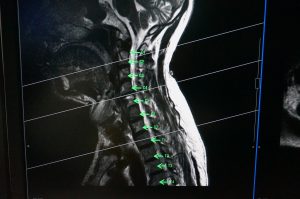

そして今回、「脊椎ラベリング」機能が新たに加わった。読影をする際、毎回脊椎番号をつけるのは、煩雑な作業だった。そこで、より効率的に作業が進められるよう、ラベリングのアノテーション機能が追加された。

開始したい脊椎ラベルの番号と、頭か尾、どちらの方向からラベリングしたいのか設定することができる。ラベリング後、axialやcoronal断面と連動しながら、今どの脊椎が画面上に表示されているか確認が可能だ。